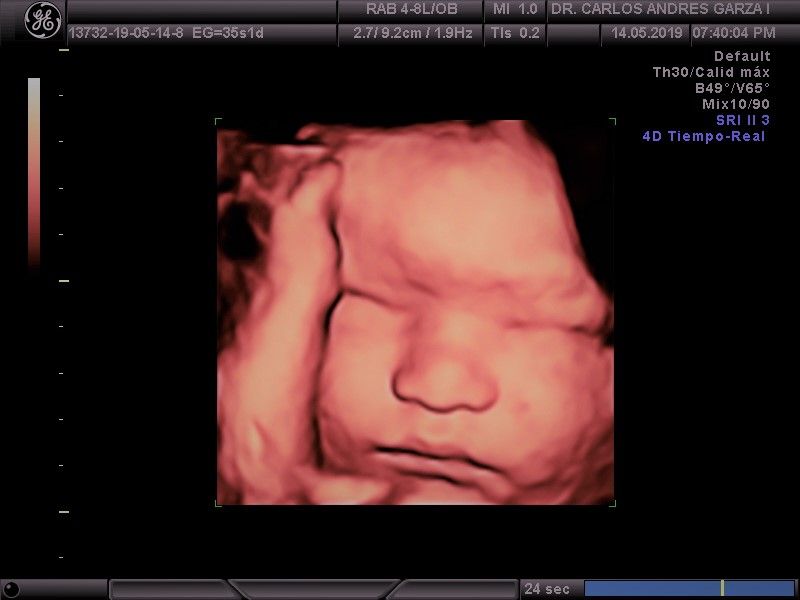

Ultrasonido 4D

!Conoce a tu bebé hoy¡ Se trata de la última tecnología en ecografía o ultrasonido a nivel mundial, que consiste en un procesamiento de reconstrucción digital de imágenes para formar una sola imagen en 4 dimensiones, permitiendo así poder visualizar cualquier estructura tal cual la estuviésemos viendo directamente el rostro de tu bebé, antes de nacer. Con esta nueva generación de tecnología del ultrasonido puedes observar datos mas detallados de su bebé, sus movimientos, gestos, risas, bostezo, etc... tal como si lo tuviera en sus brazos. En el pasado los papas no conocían la cara de su bebe hasta que naciera.